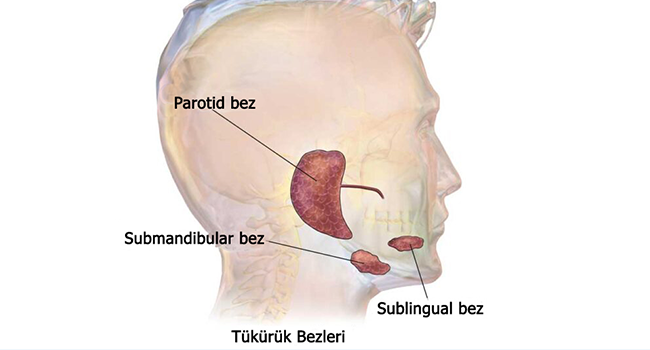

Koku (olfaksiyon) ve tat (gustasyon) duyuları, hem yaşam kalitesi hem de sağlıklı beslenme için önemli duyulardır. Bu duyularda oluşan azalma, kayıp veya algı bozuklukları; enfeksiyonlar, alerjiler, burun tıkanıklığı, sinüzit, sistemik hastalıklar veya sinir sistemi ile ilgili problemler nedeniyle ortaya çıkabilir. Koku ve tat bozuklukları bazen geçici, bazen de kalıcı olabilir. Erken tanı ve doğru tedavi, iyileşmede kritik rol oynar.

Koku ve Tat Bozukluklarının Nedenleri

1. Enfeksiyon ve Üst Solunum Yolu Hastalıkları

Bu durumlarda burun tıkanıklığı ve mukoza iltihabı, koku sinyallerinin iletimini zorlaştırır.

2. Burun ve Sinüs Problemleri

- Polipler

- Septum deviasyonu

- Konka hipertrofisi

- Kronik sinüzit